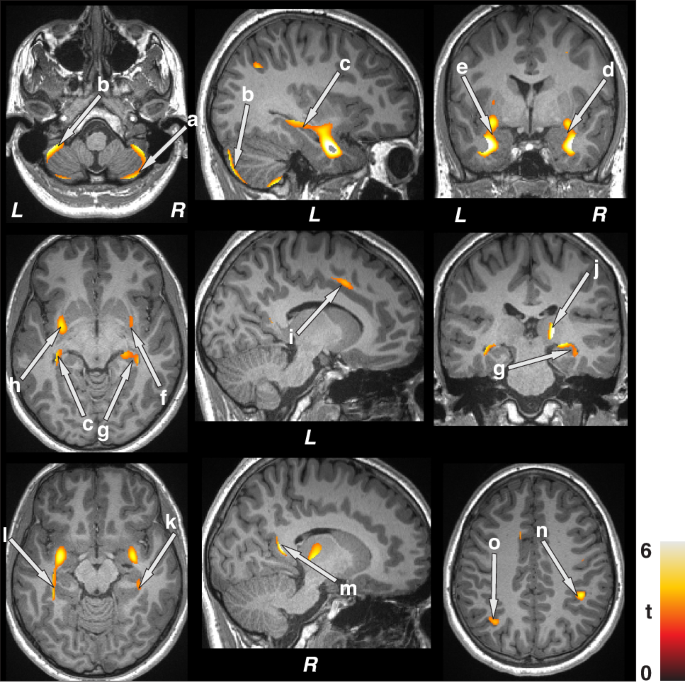

These sites with increased gray matter volumes included the bilateral cerebellar cortex (a, b), hippocampus (c, g), amygdala (d, e), putamen (f, h), mid (i), and posterior (m) cingulate, right thalamus (j), bilateral para-hippocampal gyrus (k, l), and parietal cortices (n, o). All images are in neurological convention (L left, R right). Color bar indicates t-statistic values.

Regional gray matter volume changes

Multiple brain areas showed increased regional gray matter volume in children with epilepsy compared to control subjects (Fig. 1; covariates, age, sex, and BMI), including the bilateral cerebellar cortex (a, b), hippocampus (c, g), amygdala (d, e), putamen (f, h), mid (i), and posterior (m) cingulate, right thalamus (j), bilateral para-hippocampal gyrus (k, l), and parietal cortices (n, o). Decreased volumes were prominent in more-rostral regions that serve prominent roles in CO2 and O2 integration, including the posterior thalamus (Fig. 2 e, m), and blood pressure regulation, including the bilateral ventral medial frontal cortices (c, k), bilateral insula (a, b) and hypothalamus (d, j). Decreased gray matter volumes also appeared in inferior (h, q), mid (i, r), and superior (g, p) temporal cortices, lingual gyrus (f, l), and caudate (n, o) in pediatric patients with epilepsy compared to controls (Fig. 2). Similar regions emerged showing increased gray matter volumes in children with epilepsy compared to controls after controlling for additional covariates including symptomatic epilepsy, nocturnal seizures, and neurodevelopmental disabilities (Supplementary Fig. 1). However, fewer sites with decreased gray matter volumes appeared in children with epilepsy compared to healthy controls after accounting for additional covariates (Supplementary Fig. 2).